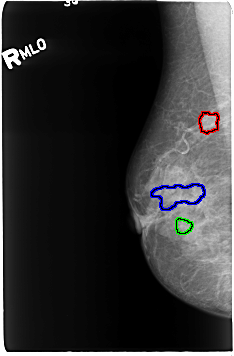

B_3050_1.RIGHT_MLO

FILE: B_3050_1.RIGHT_MLO.OVERLAY

TOTAL_ABNORMALITIES 3

ABNORMALITY 1

LESION_TYPE MASS SHAPE IRREGULAR MARGINS OBSCURED-ILL_DEFINED

ASSESSMENT 4

SUBTLETY 3

PATHOLOGY MALIGNANT

ABNORMALITY 2

LESION_TYPE CALCIFICATION TYPE PUNCTATE-PLEOMORPHIC-FINE_LINEAR_BRANCHING DISTRIBUTION SEGMENTAL

PATHOLOGY UNPROVEN

ABNORMALITY 3